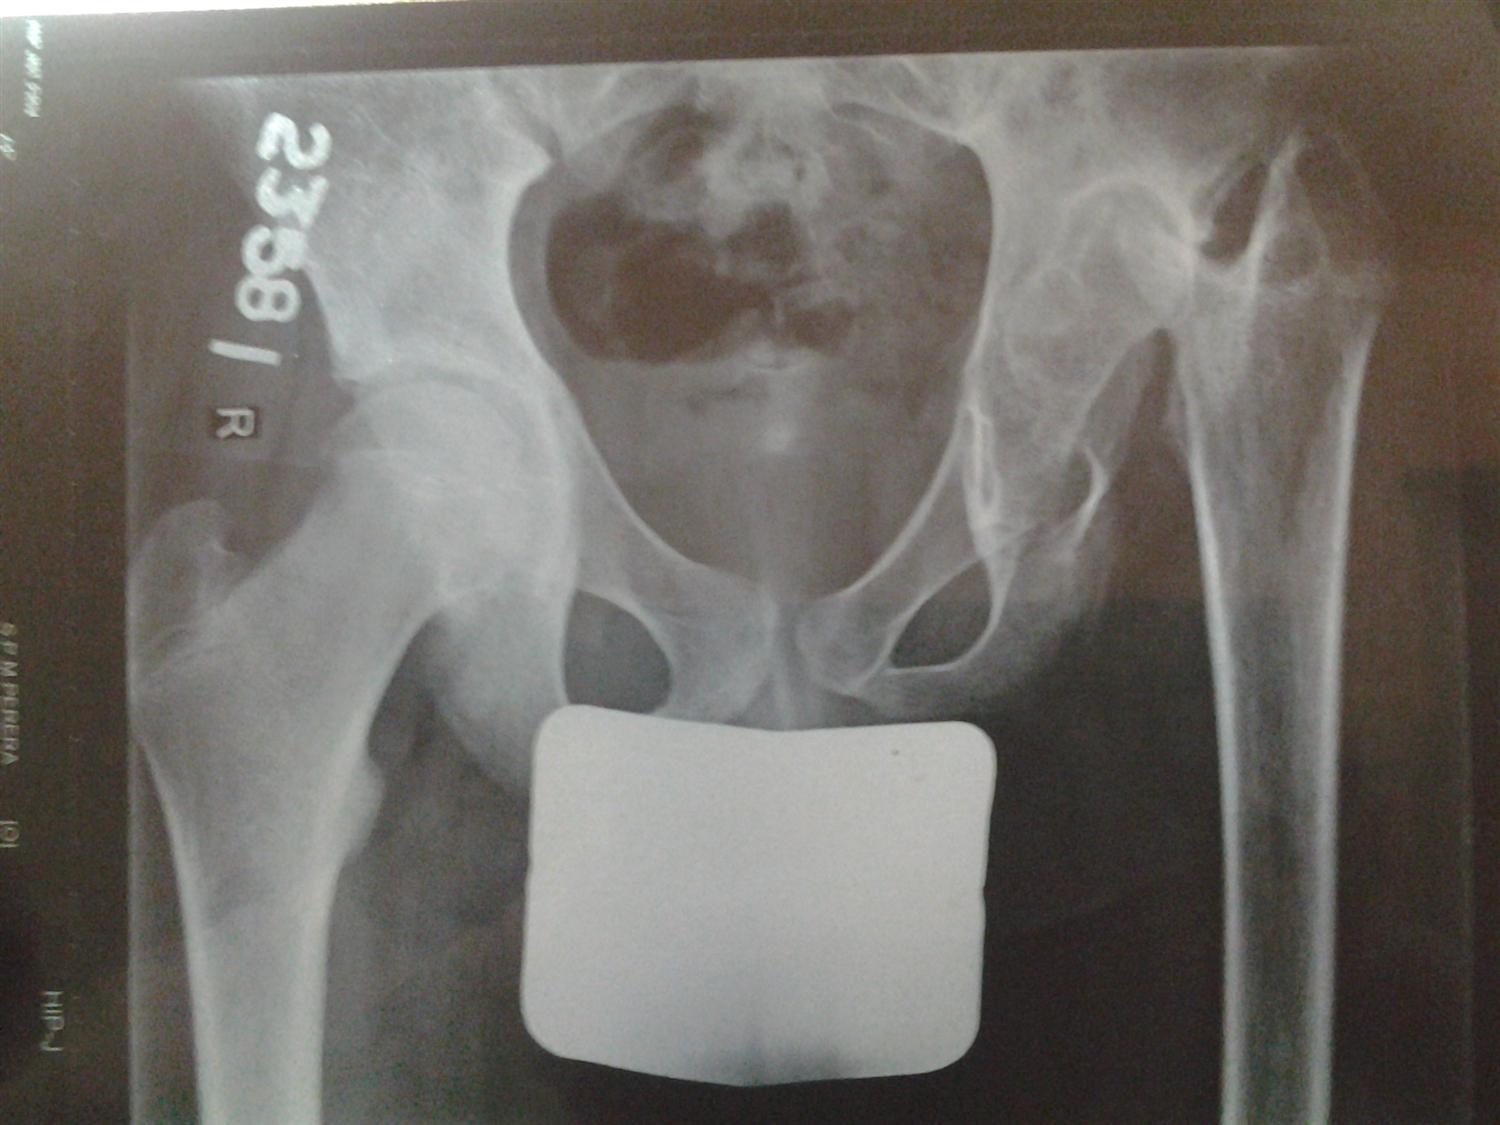

Hip Septic Arthritis Pediatric Pediatrics Septic Arthritis Pediatrics septic arthritis is an infection in the joint fluid (synovial fluid) and joint tissues. Septic arthritis affects children of all ages; — septic arthritis of the pediatric hip joint (sah) is a rare but serious orthopedic emergency requiring. — the term septic arthritis usually refers to bacterial arthritis or fungal arthritis, but bacterial joint infections are. . Septic Arthritis Pediatrics.

Hip Septic Arthritis Pediatric Pediatrics Orthobullets Septic Arthritis Pediatrics septic arthritis is an infection in the joint fluid (synovial fluid) and joint tissues. — paediatric septic arthritis can be treated by arthrocentesis (articular needle aspiration) with or without irrigation,. — septic arthritis of the pediatric hip joint (sah) is a rare but serious orthopedic emergency requiring. It occurs more often in children than adults. —. Septic Arthritis Pediatrics.

Hip Septic Arthritis Pediatric Pediatrics Orthobullets Septic Arthritis Pediatrics septic arthritis is an infection in the joint fluid (synovial fluid) and joint tissues. — septic arthritis is a surgical emergency. — paediatric septic arthritis can be treated by arthrocentesis (articular needle aspiration) with or without irrigation,. — the term septic arthritis usually refers to bacterial arthritis or fungal arthritis, but bacterial joint infections are. Septic. Septic Arthritis Pediatrics.

Pediatric Septic Hip Arthritis What You Need to Know Septic Arthritis Pediatrics in most children, septic arthritis only affects one joint in the body. — septic arthritis is a surgical emergency. — septic arthritis of the pediatric hip joint (sah) is a rare but serious orthopedic emergency requiring. The most common sites for septic arthritis include the: septic arthritis is an infection in the joint fluid (synovial fluid). Septic Arthritis Pediatrics.